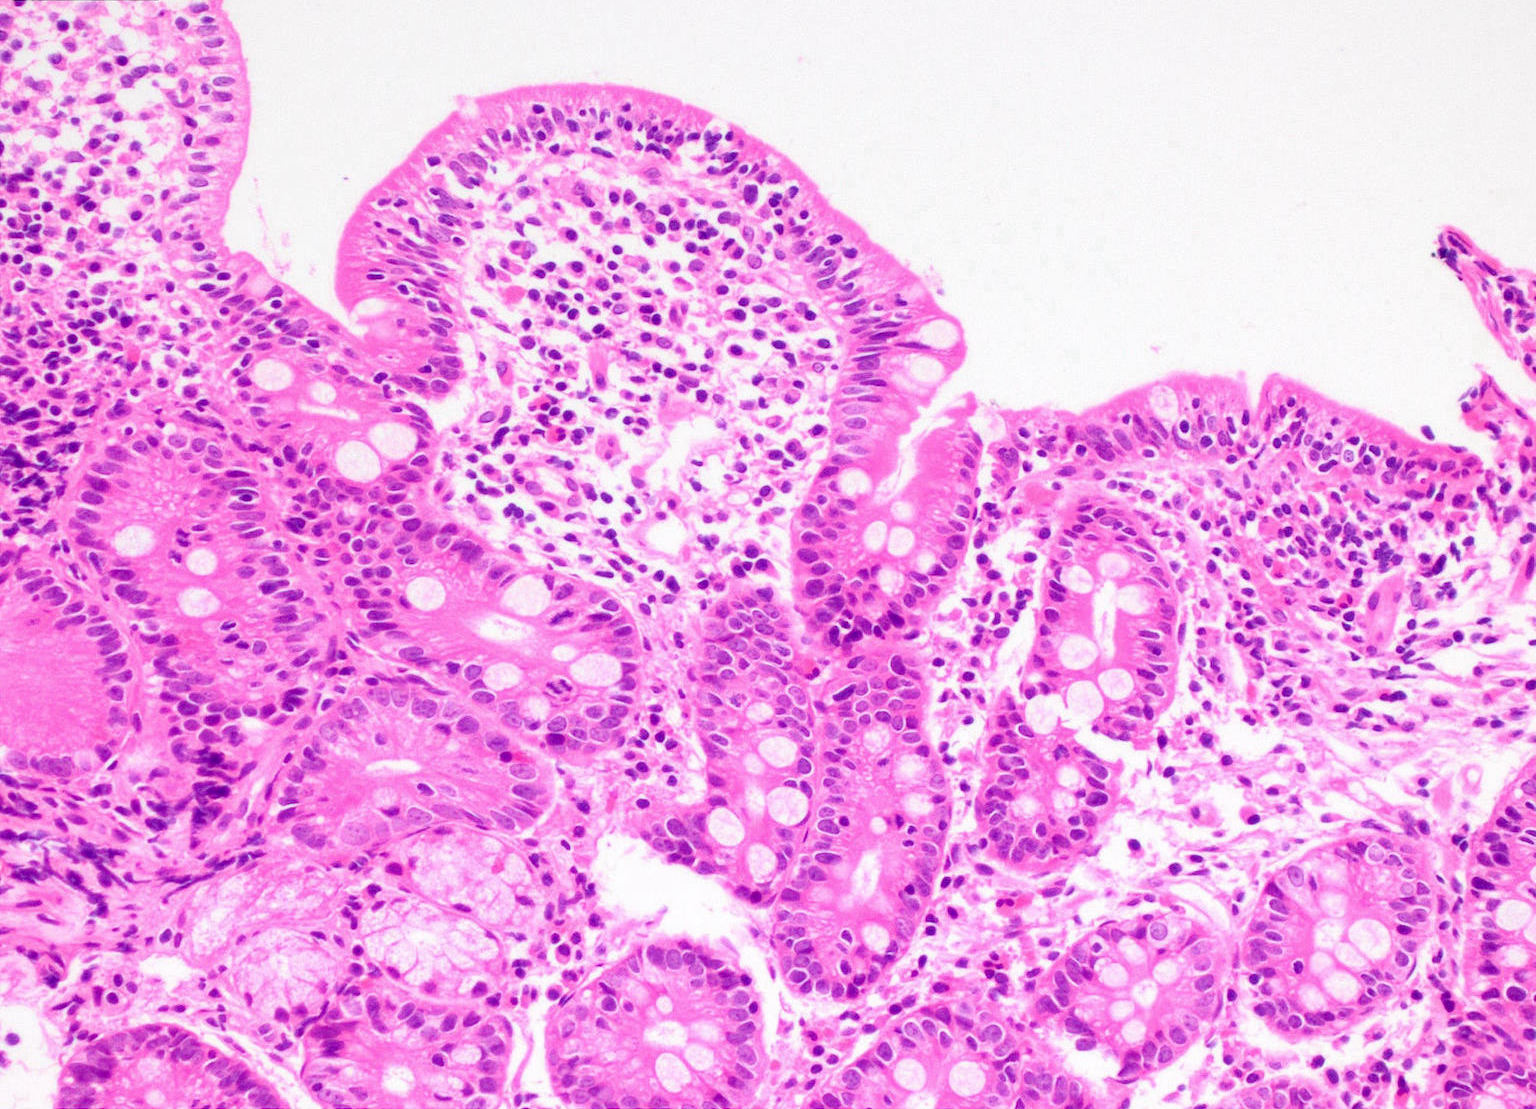

Microscopic (histologic) description

- Histological elementary lesions (Dig Liver Dis 2011;43:S385, Semin Diagn Pathol 2014;31:124):

- Increased intraepithelial T lymphocytes (IEL):

- 25 - 29 IEL/100 enterocytes is considered borderline

- > 30 IEL/100 enterocytes represents a pathological lymphocytosis

- Decreased enterocyte height, flattening of enterocytes, intracytoplasmic vacuolation and reduction or absence of brush border are suggestive but not specific

- Crypt hyperplasia:

- Extension of the regenerative epithelial crypts associated with changes in the presence of more than 1 mitosis per crypt

- Villous atrophy:

- Decrease in villous height, normal villous:crypt ratio (3:1) until total disappearance of villi

- This assessment requires proper orientation of the biopsies

- Increased intraepithelial T lymphocytes (IEL):

- Diagnostic categories are based on these elementary lesions:

- Modified Marsh-Oberhuber classification of histologic findings in celiac disease

- Simplified systems (Corazza & Villanaci or Ensari), which may be more reproducible (Arch Pathol Lab Med 2010;134:826, Pathol Res Pract 2016;212:1174)

- Different grades of duodenal mucosal lesions:

- Grade A / type 1: increased intraepithelial lymphocytes but no villous atrophy

- Grade B1 / type 2: villi still present but shortened

- Grade B2 / type 3: complete villous atrophy

Microscopic (histologic) images